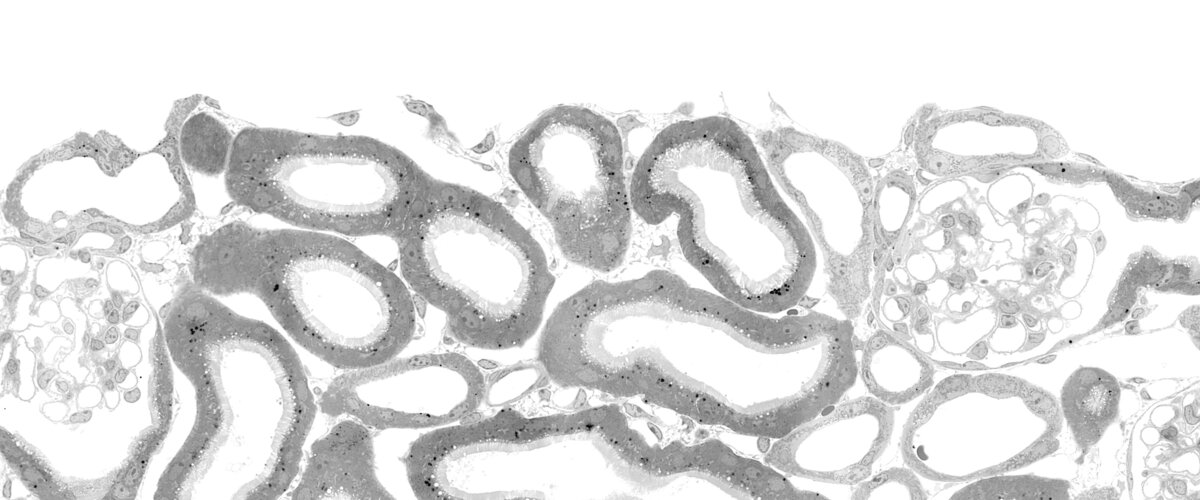

Our groups's scientific focus is on the function of ion channel and membrane transport proteins and elucidating the pathophysiology of monogenic diseases. We investigate these mechanisms primarily in two organs: the adrenal cortex and the kidney. This combination of basic research and medical issues is also the focus of teaching in the Molecular Medicine (B.Sc.) program.